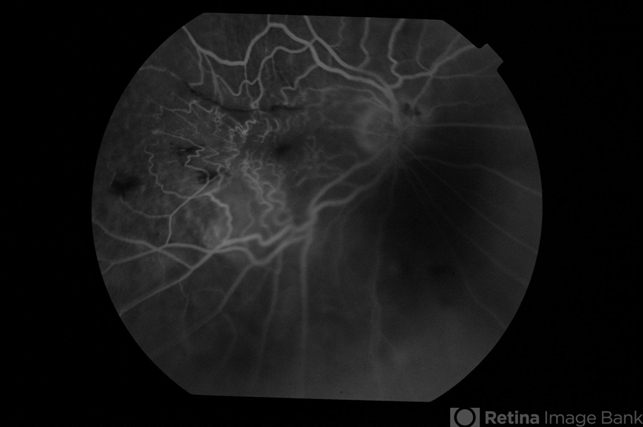

- Lignocaine retinal toxicity

- Right eye fluorescein angiogram of a 70-year-old male 3 weeks after inadvertent globe penetration with peribulbar anaesthesia needle and intraocular injection of lignocaine. There is an occluded retinal arteriole indicating macular ischaemia underlying the clinically obvious epimacular membrane.